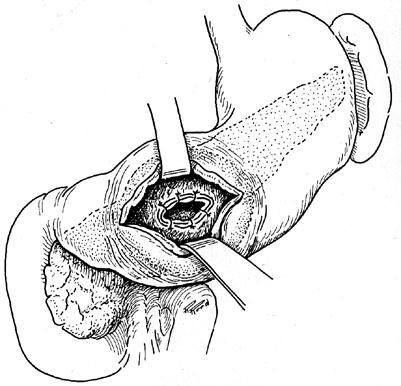

С целью ликвидации кист, полость которых поддерживалась благодаря сообщению ее с протоковой системой ПЖ, на протяжении длительного времени применялось так называемое внутреннее дренирование кист путем анастомозирования их с просветом желудка, двенадцатиперстной или тощей кишки (цистогастростомия, цистодуоденостомия, цистоеюностомия с выключенным из пищеварения участком тощей кишки (рис. 165, 166)).

Рис. 165. Наложение цистогастроанастомоза